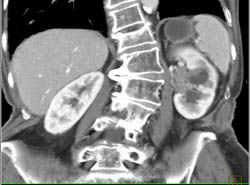

Recurrent Renal Cell Carcinoma in Left Renal Bed